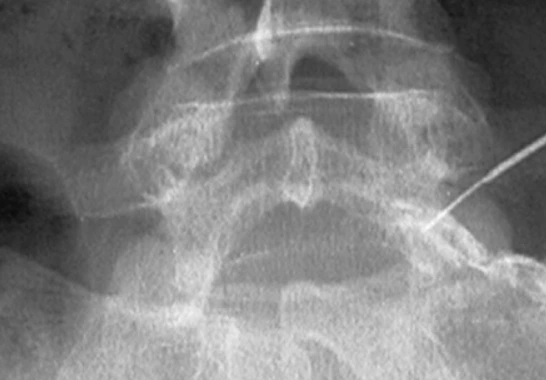

경막외 신경성형술

디스크나 협착증의 대표적인 비수술적 치료법으로 지름이 1mm 정도의 아주 작은 카테터관을 신경과 디스크 사이로 정확하게 삽입하여 통증의 원인인 염증을 제거하고 유착을 박리해 신경의 부종과 압박을 풀어주는 치료입니다.

특히 고령의 환자나 고혈압, 당뇨, 심장병 등 내과적 합병증이 있는 환자도 안전하고 문제없이 시술할 수 있는 방법이지요.